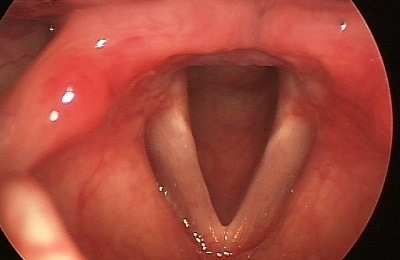

Пациент 11 лет, был направлен на прием к лору с жалобами на затрудненное дыхание, сухость в горле и осиплость голоса. При осмотре: общее состояние ребенка не нарушено, слизистая гортани гиперемирована, отечна, голосовые складки розовые, смыкаются не полностью. Диагноз: катаральный острый ларингит.

Назначено лечение: голосовой покой, диета, гортанные заливки с масляным раствором витамина Е, щелочные ингаляции и Эфизол (пастилки для рассасывания).

Через неделю состояние ребенка нормализовалось и он вернулся к привычному образу жизни.